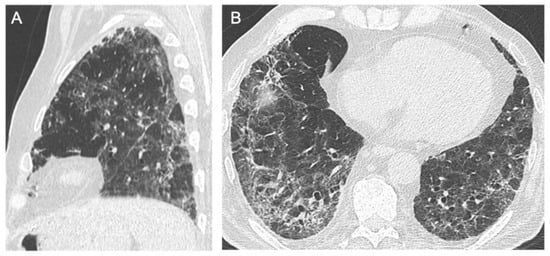

3.1.3. Linear Bands

3.1.4. Reticulations

3.1.5. Bronchiectasis/Bronchiolectasis

3.1.6. Loss of Pulmonary Volume